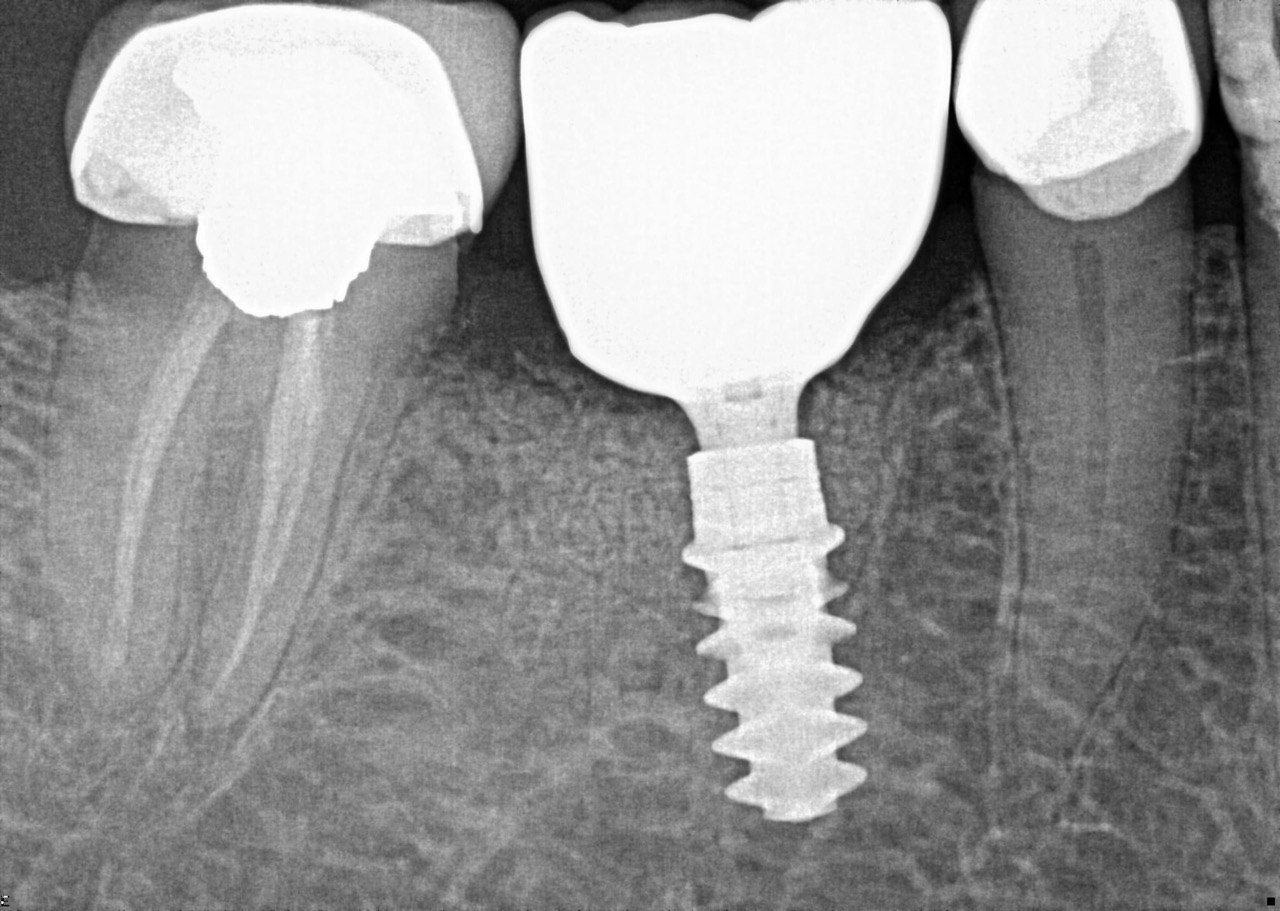

Question 21: What option is can be selected for distal tooth # 4.6?

Question 22: Which surface shows defective restoration?

Question 23: Which surface shows overhang?

Question 24: Which surface shows defective restoration?

Question 25: Which surface shows open margin?

Question 26: What option cannot be selected for mesial tooth surface # 2.8?

Question 27: What options cannot be seen in this X ray?

Question 28: What is the best option that describe distal surface of tooth # 3.5?

Question 29: What options cannot be seen in this X ray?

Question 30: What options can be selected for the tooth # 4.2?